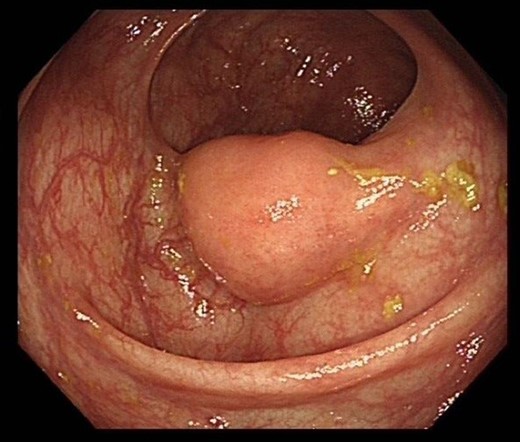

Previous colonoscopy, 4 years prior, had found several benign polyps. On recent colonoscopy, a 2 cm submucosal lesion within the ascending colon was identified and thought to be a lipoma (Figure Xa and Xb). Biopsies taken at the time were found to be benign with only oedematous large bowel mucosa seen, however these were superficial and no submucosal tissue was present (Figs 1–7).

Colonoscopy image of the ascending colon showing submucosal lesion.